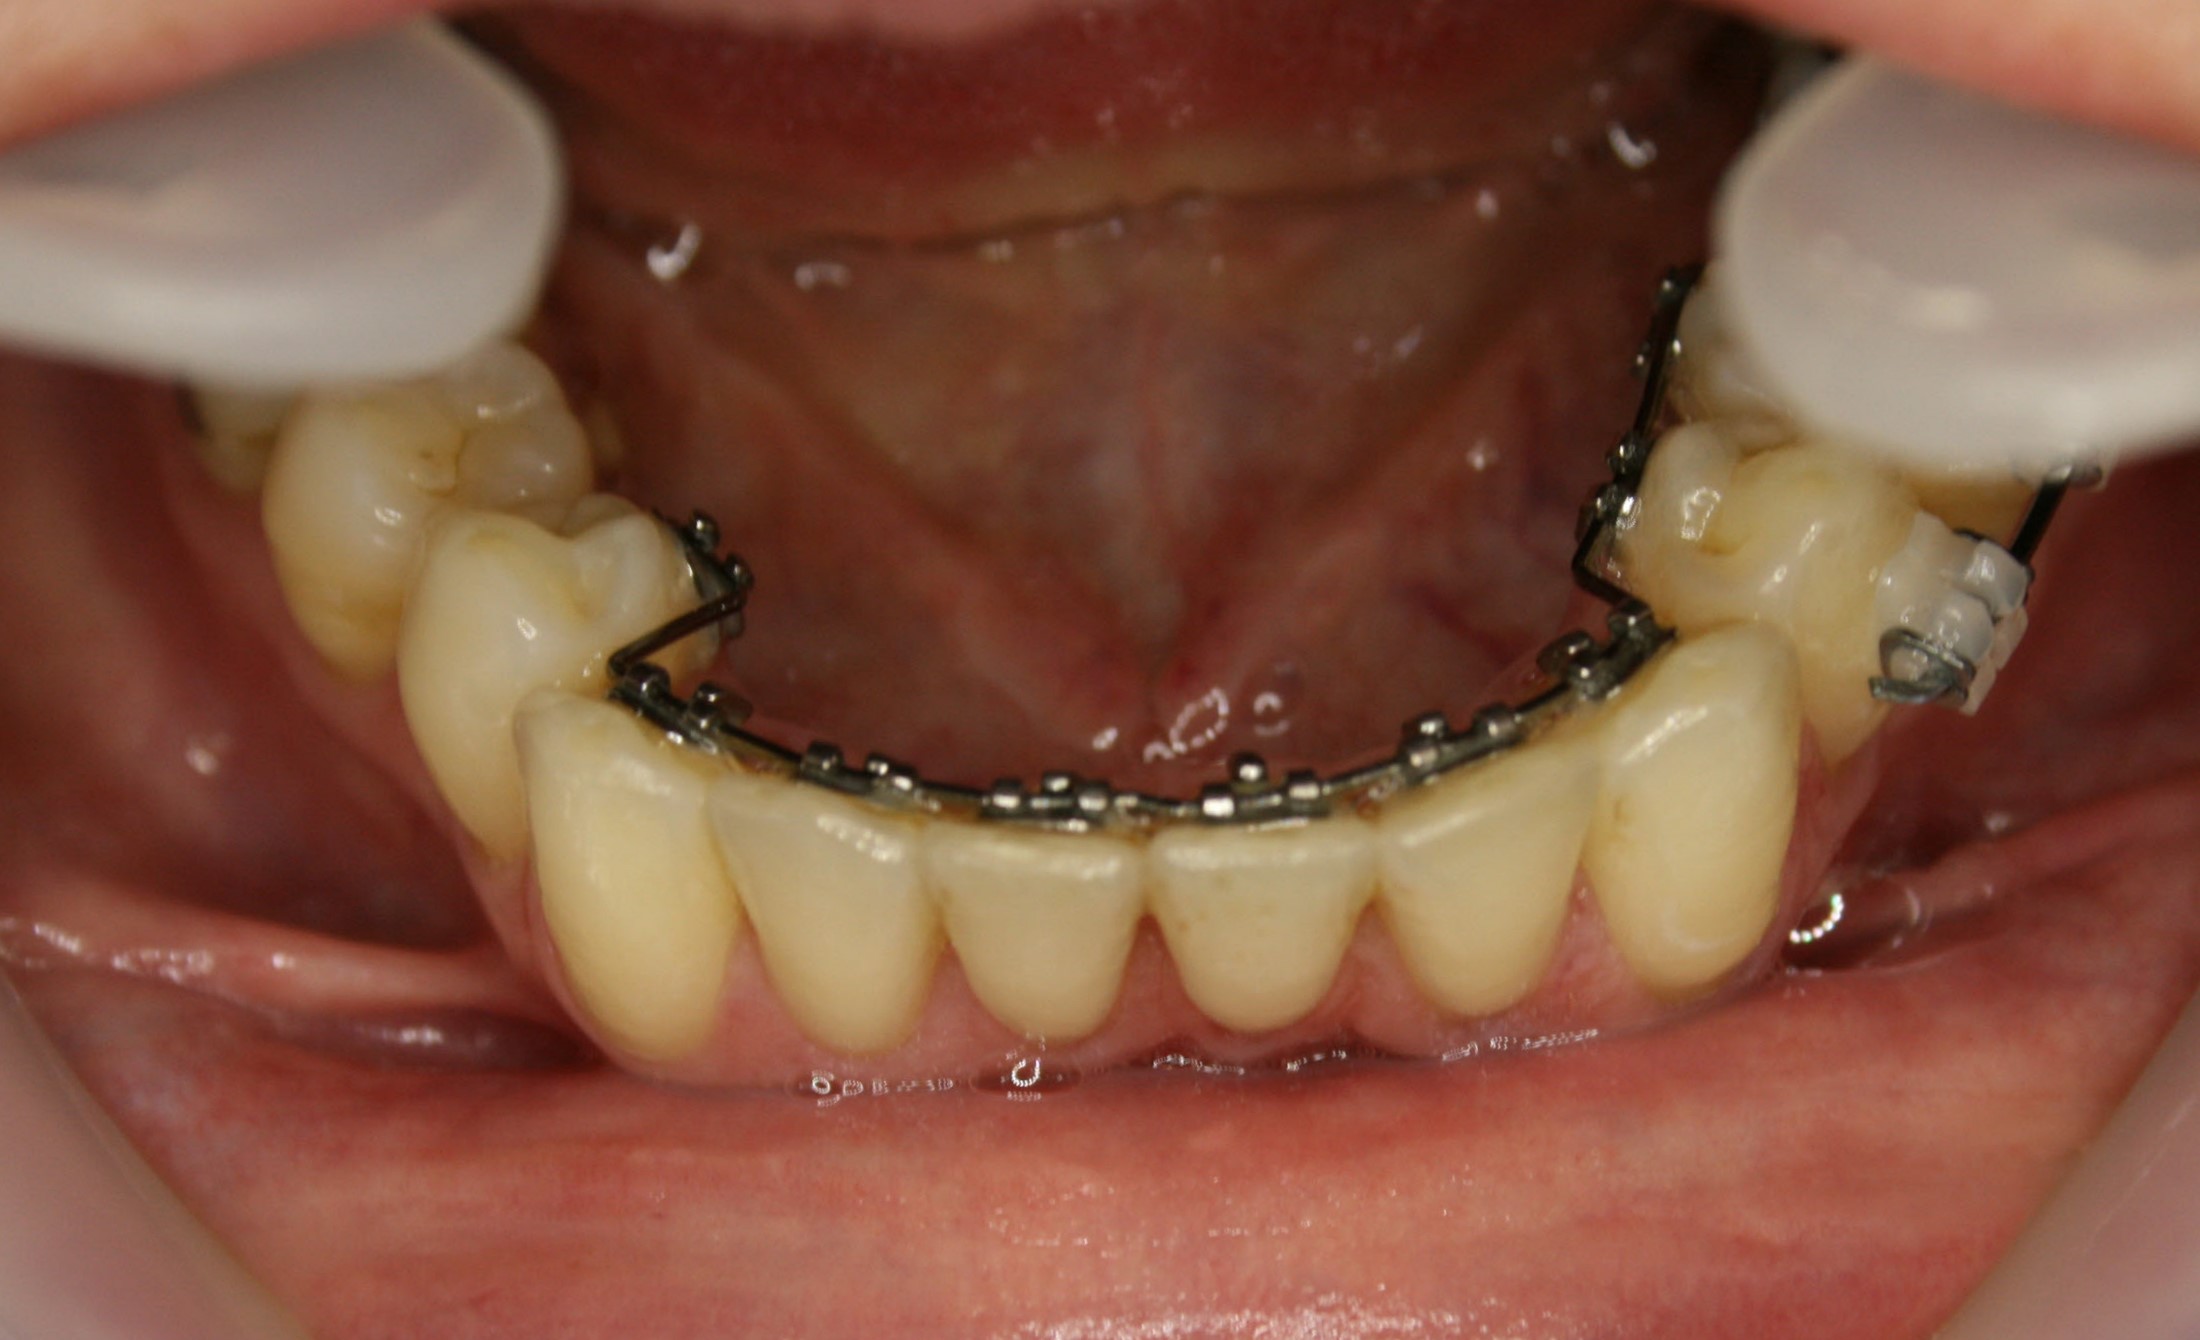

Im Unterkiefer kam auch eine auf der Innenseite der Zähne befestigte Zahnspange zum Einsatz; da es keine Lückenschlußaufgabe zu bewältigen gab, konnte ein einfacheres System verwendet werden. Es ist angenehmer für die Zunge, weil es flacher ist als das aufwendigere System im Oberkiefer. Siehe hierzu auch die Ausführungen im Abschnitt „Behandlungsmethoden – Welche Arten von Zahnspangen gibt es". Die Ausformung des Unterkiefers war nach einem Jahr und 2 Monaten abgeschlossen.